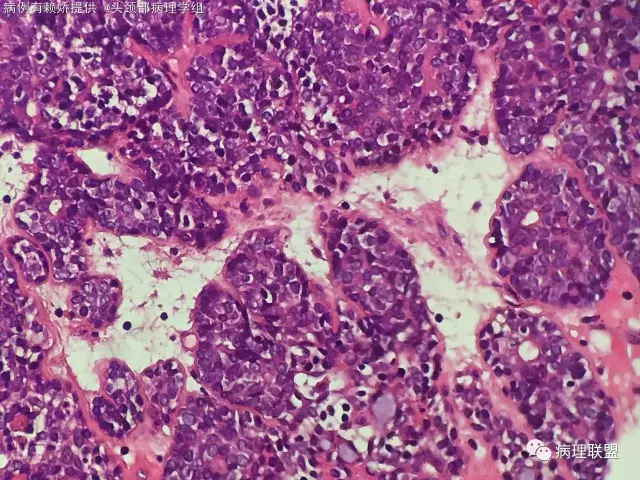

男,54岁,后颈部肿块10年(病例由赖娇 提供,致谢!)

小汗腺螺旋腺瘤

@梅宜兼 本例明显呈上皮巢排列,肿瘤由两种细胞构成外层呈栅栏状排列细胞小核染色深,另一种为咯略大淡染隐约可见小核仁的腺上皮细胞!间质可富裕血管,水肿及少量基底膜样物质!另外还有个特点散在淋巴细胞!该肿瘤肉眼看切片给人第一印象像个淋巴结!